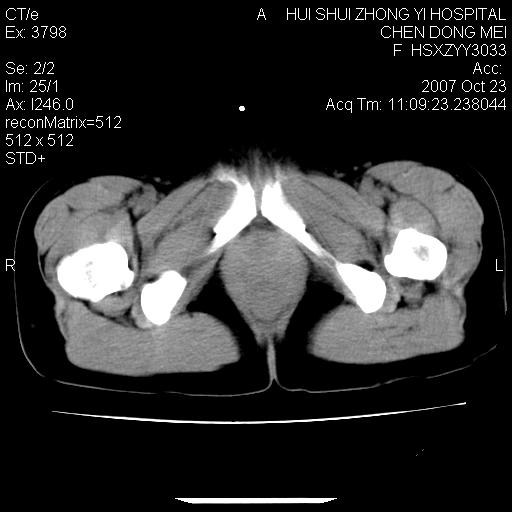

标题: CT10156:女.43岁,发现中下腹部包都块2年 [打印本页]

标题: CT10156:女.43岁,发现中下腹部包都块2年

发现中下腹部包都块2年。2年来月经不规律。

腹腔及盆腔恶性肿瘤可能性大,腹膜后可见肿大的淋巴结影,恶性畸胎瘤?

腹腔巨大软组织密度影,边缘光滑,包膜完整,内囊变坏死。腹膜后及盆腔内淋巴结肿大。结合病史考虑卵巢癌可能性大。

病灶内可见脂肪密度影,考虑畸胎瘤可能性大

病变巨大,呈囊实性改变,包膜较厚且完整,内见分膈,周围脏器明显受压移位,病变与左侧附件关系密切,考虑来源左侧附件的囊腺瘤,不除外癌变可能;畸胎瘤可能性较小。

病变巨大,呈囊实性改变,包膜较厚且完整,内见分膈,周围脏器明显受压移位,病变与左侧附件关系密切,考虑来源左侧附件的囊腺瘤,盆腔内见肿大淋巴结,不除外癌变可能。